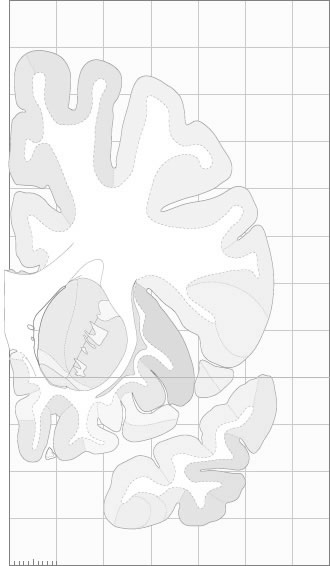

Frontal sections (Nissl) from the Atlas Brain: Gallery Slice Single

-17,9 mm

Slice ID: r2-0520

Plate NR: 10-11

Position: -17,9 mm